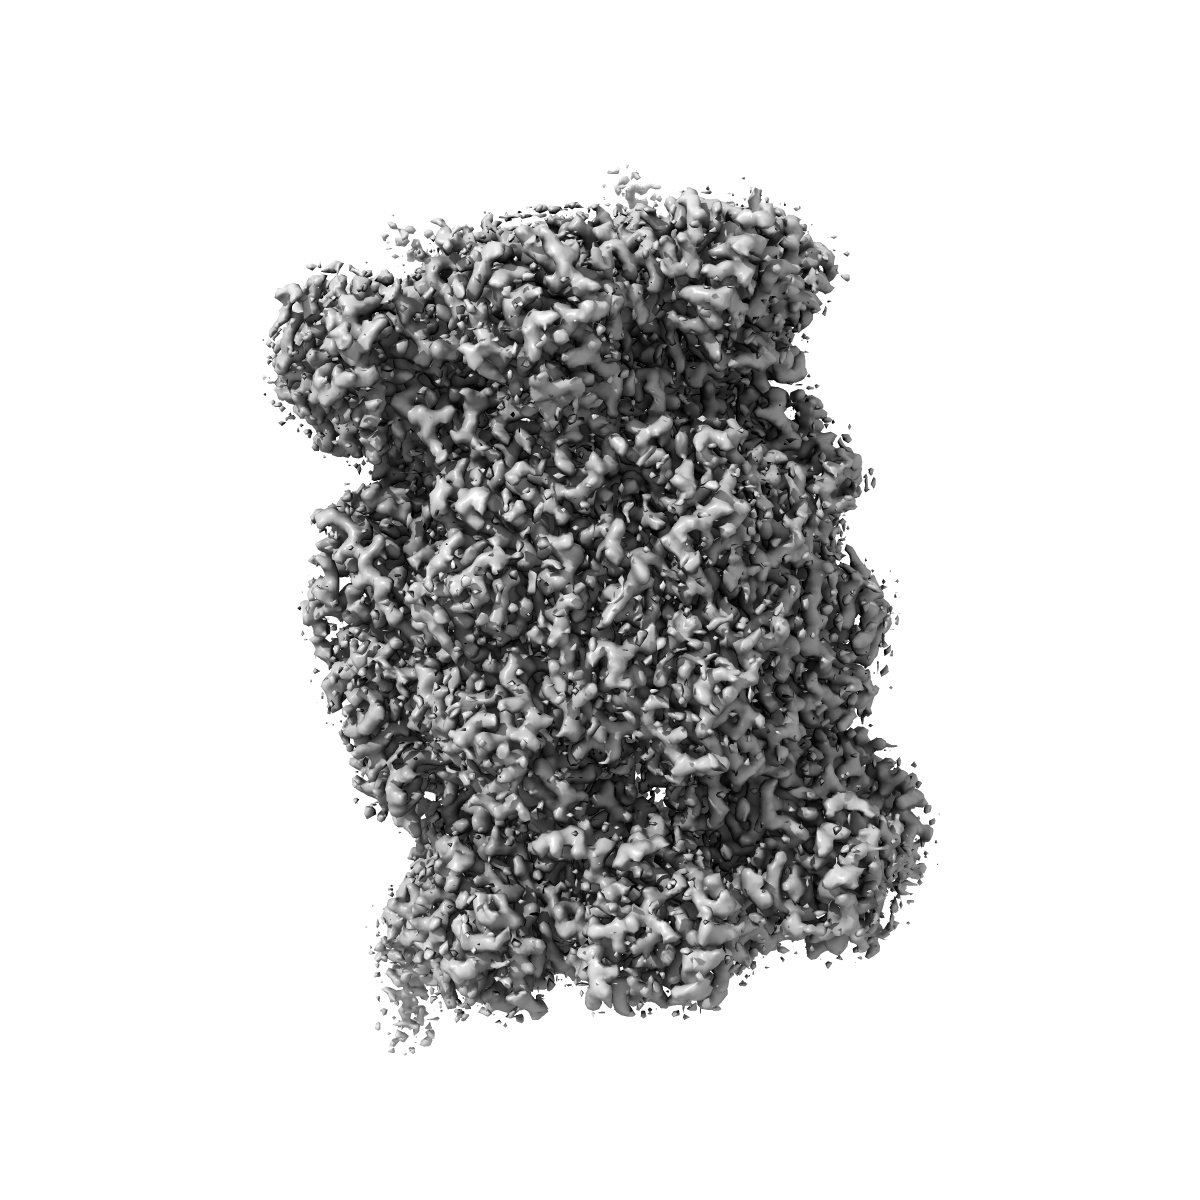

EMD-4590

Leishmania tarentolae proteasome 20S subunit complexed with GSK3494245

Single-particle2.8 Å

Deposition: 01/02/2019Map released: 17/04/2019

Last modified: 15/05/2024

Fitted models: 6qm7

Deposition Authors: Rowland P, Goswami P

Preclinical candidate for the treatment of visceral leishmaniasis that acts through proteasome inhibition.